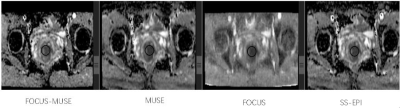

Figure 3. Comparisons of image quality of SS-, FOCUS-, MUSE-, and FOCUS MUSE- DWI. Diffusion-weighted images at b=800 s/mm2) with the corresponding ADC maps are arrayed. Image quality with FOCUS MUSE-DWI was significantly different from SS-DWI and FOCUS-DWI in severity of artifacts, sharpness of boundaries, interslice signal homogeneity and overall image quality (p < 0.05). FOCUS MUSE-DWI was slightly superior to the MUSE-DWI in overall image quality (p > 0.05).